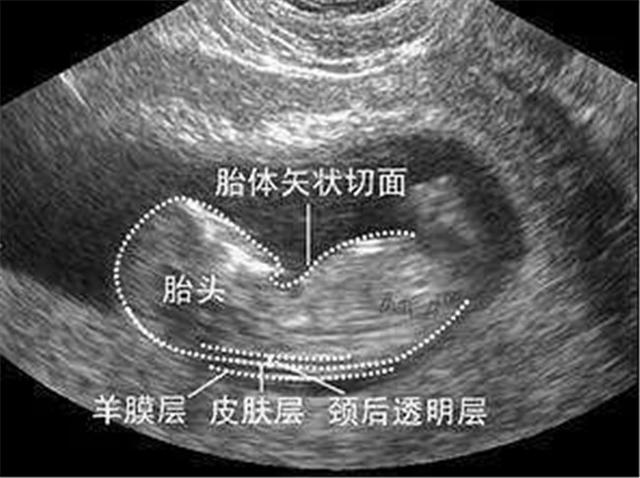

一、NT的“真相”:NT是颈项透明层的英文缩写(Nuchal Translucency , NT) , 指胎儿脖子后方皮肤下面积聚的组织内液的厚度 , 它是怀孕早期筛查胎儿先天愚型一种方法 。

2、NT 的正常值:NT是通过B超进行测定的 , 正常值﹤3mm , 如果≧3mm , 则为异常 , 孕妈们就应该引起重视 。